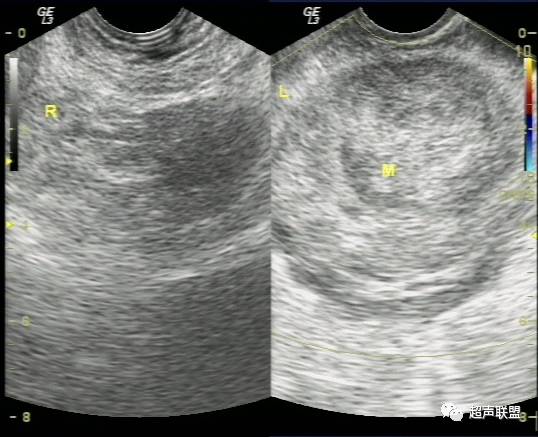

(1)子宫增大或轻度增大,子宫内膜不同程度增厚,宫内未见妊娠囊。

(2)一侧附件区可探及不均质包块,包块形态欠规则,边界不清楚,回声紊乱。

(2)卵巢黄体破裂一般无盆腔包块,但如于黄体附近形成血凝块,与破裂黄体混合形成包块时,是最不易与宫外孕破裂鉴别的疾病之一,特别是与卵巢内异位妊娠破裂不易鉴别。因其声像图均表现为附件区混合性包块,阴道检查则发现包块均位于卵巢内,盆腔液性暗区均有密集点状回声等出血征象。但黄体破裂子宫大小正常,子宫内膜为分泌期内膜,而无蜕膜反应性增厚。其临床资料无停经史,破裂腹痛时多发生于月经中后期,常因腹部重击、及妇科检查引起。盆腹腔积液相对较少,而尿或血HCG检查常阴性。

(3)附件炎性包块,患者多为持续下腹疼痛,无突然腹痛加重史,多伴较多的黄色白带而非不规则阴道流血,部分伴发热,无明显腹膜刺激征,血象多增高。临床亦无停经史,查尿HCG阴性。超声检查其子宫体积可稍大,肌层回声不均,无子宫内膜增厚。阴道超声检查可发现其盆腔液中有粗细不一的炎性渗出纤维析出性条状光带,而非密集点状回声。

(4)卵巢囊肿破裂,患者过去多有囊肿病史,突发剧烈腹痛亦多有重击、及妇科检查等诱因。巧克力囊肿则多有痛经病史,由于其囊壁较厚一般不容易破裂,但当月经期出血量多时仍可以破裂。超声检查发现其子宫大小亦多正常,子宫内膜不厚,患者亦无停经史,尿HCG检查阴性。  总之,宫外孕破裂出血是妇产科最常见的急腹症之一。出血量大者,病情特别危急,需要立即做出诊断和鉴别诊断,以便采取适当而有效的治疗措施。对于一个临床主要表现为下腹剧烈疼痛,超声表现为附件或盆腔混合性包块,伴有盆腔甚至腹腔积液的妇科急症患者,检查者应该想到上述疾病。超声声像图注意观察子宫大小、子宫内膜厚度、盆腔积液的内部回声等。并尽可能详细询问月经史、性生活史及临床病史,结合尿或血HCG检查、血常规检查等,进行综合分析判断。随着超声仪技术的发展,阴道彩色多普勒检查的应用,宫外孕包块内滋养层血流的检测,将更有助于宫外孕破裂的诊断及鉴别诊断。